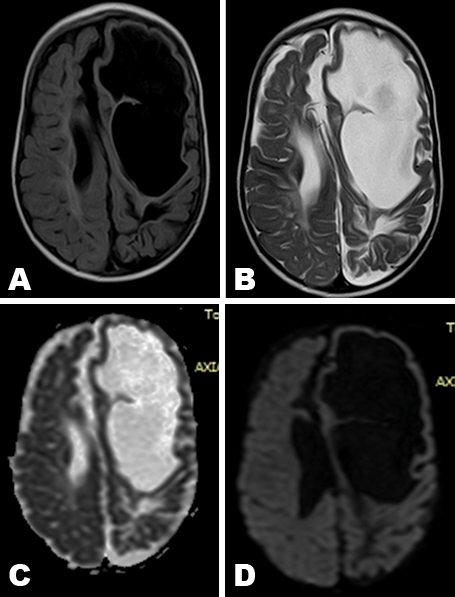

A two-year-old Sudanese male was presented in neurology clinical department with delayed growth and development, and seizures. Then referred to radiology department. Non-contrast magnetic resonance imaging scan of brain axial, saggital and coronal. T1-weighted, T2-weighted, fluid attenuation inversion recovery (FLAIR) and diffusion weighted imaging (DWI) were done (Figure 1A–D). Images showed well defined intracranial cyst on left frontoparietal region connected with the ipsilateral lateral ventricle, associated with diffuse brain atrophic changes in term of dilatation of ventricular system, prominent cortical sulci and dilated extra-axial cerebrospinal fluid spaces.

The intracranial cyst margin not lined by a grey matter and is associated with a small amount of adjacent FLAIR hyper-intensities, no restricted diffusion noted in DWI. No soft tissue mass lesions. No intracerebral blood degradation products. Normal brainstem and cerebellum. Findings are impressive of congenital diffuse brain atrophic changes associated with significant left sided porencephalic cystic changes as described above.

Figure 1: Magnetic resonance imaging of brain. Axial images of porencephalic cyst on left frontoparietal region connected with the ipsilateral lateral ventricle (A) FLAIR image, (B) T2-weighted image, (C) Apparent diffusion coefficient image, and (D) Restricted diffusions image.